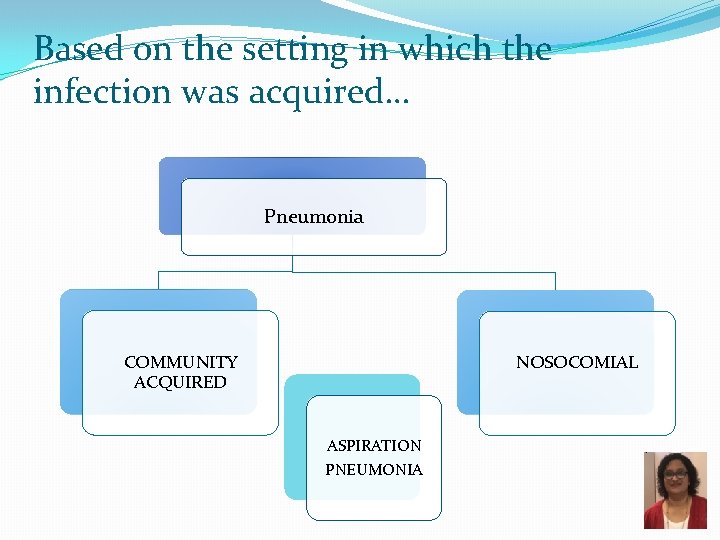

Types of Pneumonia Clinical findings Onset Acute Chronic Typical pneumonia Atypical pneumonia Setting Community acquired Nosocomial

Based on the setting in which the infection was acquired… Pneumonia NOSOCOMIAL COMMUNITY ACQUIRED ASPIRATION PNEUMONIA